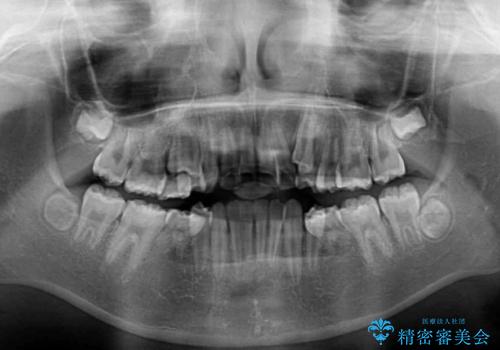

乳歯が3歯残っており、下顎は左右ともに後続永久歯がない状態でした。

口元が突出しており、口が閉じにくかったため、乳歯を含め上下5歯を抜歯して矯正治療を行うこととしました。

下顎の乳歯は永久歯と比べて幅が大きいため、抜歯した場合のスペースが大きく、治療には長期間を要することが一般的です。